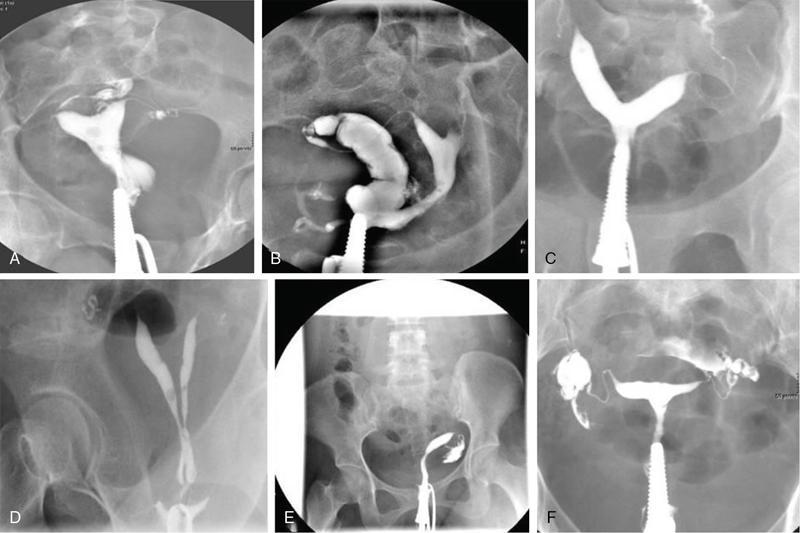

MÜLLERIAN DUCT ANOMALIES Rajani Gorantla Müllerian ducts are a pair of tubular structures that give rise to uterus, cervix, fallopian tubes and upper two-thirds of vagina. Disruption or failure of normal development can result in occurrence of Müllerian duct anomalies (MDAs). These are commonly associated with other congenital anomalies of urinary tract and ovaries due to the close relationship between the development of mesonephric and paramesonephric ducts; few patients also have associated skeletal system anomalies. The prevalence of MDAs in an unselected population was 5.5%; 8% among the infertile women, 12.3% in women with a history of recurrent pregnancy loss and 24.5% in women with miscarriage and infertility. Most of the patients with MDAs are asymptomatic and found incidentally on imaging for any other gynaecological problems, in evaluation of a patient with renal, skeletal or abdominal wall abnormalities. In symptomatic women, complains are related to the type, severity, obstructive anomaly or nonobstructive anomaly. The symptoms can be obstetric or gynaecological related, includes recurrent spontaneous abortions, infertility, preterm labour, intrauterine growth restriction and abnormal foetal lie. Few adolescent girls may present with primary amenorrhoea, hypomenorrhoea, abnormal vaginal bleeding, cyclical pain and mass. Rarely they can present with pelvic inflammatory disease with abnormal vaginal discharge, dyspareunia and urinary tract infections. The female reproductive system develops from a pair of Müllerian or paramesonephric ducts, urogenital sinus and vaginal plate. The ovaries develop separately from the primordial ridge. It is of great importance to understand the normal stages of development, as failure or interruption of any of these stages can lead to a simple to complex spectrum of anomalies. The three stages of Müllerian duct development include: At 6–10 weeks of gestation age, two paired Müllerian ducts and Wolffian ducts formation occurs. When Y chromosome factor (testicular determining factor) is absent, the Wolffian ducts undergo degeneration. The Müllerian ducts further elongate caudally and cross the Wolffian ducts to fuse in the midline. At 10–13 weeks of gestation age, caudal and lateral fusion of the two Müllerian ducts forms primitive uterovaginal canal, which is possessed of solid tissue initially located side by side and further internal canalization leads to the formation of two channels/canals divided by a septum. At this stage, there is reabsorption of the caudal septum and forms single cervical canal and vagina lumen. In around 15–20 weeks of gestation age, complete resorption of the septum takes place in a caudocranial direction from the isthmus to fundus and development of single endometrial cavity results. The fused caudal part of Müllerian ducts gives rise to the uterus, cervix and upper two-thirds of vagina; the unfused cranial part forms the fallopian tubes (Fig. 11.14.1.1). The lower vagina develops from the urogenital sinus, which is separated from the rectum by urorectal septum around 7 weeks of gestation age. The primitive uterovaginal canal embeds into the dorsal wall of urogenital sinus and forms Muller’s tubercle. Around 13 weeks of gestation, two solid masses known as sinovaginal bulbs originate from the upper part of the Muller’s tubercle, further proliferate into the caudal end of the uterovaginal canal to become a solid vaginal plate. Later canalization or degeneration of the central cells of the vaginal plate forms the lower vagina, which is usually completed by 20 weeks’ gestation. The vertical fusion of the upper and lower vagina occurs with resorption of tissue in between and forms single vaginal cavity (Fig. 11.14.1.2). The vaginal lumen is separated from the urogenital sinus by the hymenal membrane. Just before birth, the hymen normally ruptures due to retrogression of the central epithelial cells. However, a thin fold of mucous membrane persists around the vaginal introitus. The ovaries develop separately from migration of primordial germ cells to the genital ridge. Ureteric buds develop separately and concurrently. So renal anomalies are most commonly associated with MDAs with an association of 30%–50%. Various classification systems have been proposed over the past several decades to describe MDAs. Ideally, same classification system needs to be followed by a gynaecologist, surgeon and radiologist for better communication. Buttram and Gibbons classification was suggested in 1979, and it was based upon the level of failure in normal development and segregate the anomalies into groups with similar clinical manifestations, treatment, and prognosis for foetal salvage. According to Buttram and Gibbons, the uterine anomalies were classified into six classes as described in Table 11.14.1.1. The drawback is the lack of classification of vaginal and other anomalies separately. The ASRM (previously the American Fertility Society – AFS) classification system is the most widely accepted classification worldwide over the past years and was introduced in 1988. According to this classification, MDAs are classified into seven classes (class I to class VII) as mentioned in Table 11.14.1.2. However, several limitations have been described by Grimbizis and Campo in 2010 (Fig. 11.14.1.3). The drawbacks of the ASRM classification system are as follows: Hence in 2016, an updated classification of uterine septum, that is ASRM-2016 was proposed and officially approved morphometric criteria are given for distinguishing between septate, normal/arcuate and bicornuate uteri (Table 11.14.1.3). The VCUAM classification was proposed in the year 2005. The main concern is to provide a simple, systematic, clinical classification in addition to providing a precise reflection of the entire malformation. The female genital organs were divided into the following subgroups in accordance with the anatomy: vagina (V), cervix (C), uterus (U) and adnexa (A). Associated malformations were assigned to a subgroup (M) relative to each specific organ. The disadvantage is due to its inherent complexity, and more than 56,700 individual combinations of anomalies are possible. ESHRE and ESGE established a common working group named CONgenital UTerine Anomalies (CONUTA) in order to devise an improved classification system (Table 11.14.1.4). It was published in 2013. Anatomy is the basis for systemic categorization of the MDAs. The subclasses are divided by the different degrees of uterine deformity and their clinical significance (Fig. 11.14.1.4). Cervical and vaginal anomalies are classified into independent supplementary subclasses (Figs. 11.14.1.5–11.14.1.6). For most of the clinicians, it helped as starting point for the development of guidelines for their diagnosis and treatment. The malformations are graded according to severity, U0–U5, C0–C4 and V0–V4, with U5, C4 and V4 being more severe. Class U3 incorporates bicorporeal fusion defects (didelphys and bicornuate) as this was considered as a more functional mode of classification. Arcuate uterus was not included separately, but this is categorized under normal variant into class U1c. Recent studies have demonstrated that the ESHRE/ESGE system provides an effective and comprehensive classification for almost all the currently known MDAs and overcomes the limits of previous classifications. However, there is a relative overdiagnosis of septate uterus with the application of ESHRE–ESGE criteria has been reported and which potentially might lead to unnecessary surgical overtreatment. C0 C1 C2 Normal cervix Septate cervix Double ‘normal’ cervix C3 C4 Unilateral cervical aplasia Cervical aplasia U4 V0 V1 V2 V3 Normal vagina Longitudinal nonobstructing vaginal septum Longitudinal obstructing vaginal septum Transverse vaginal septum and/or imperforate hymen V4 Vaginal aplasia C MDAs’ characterization and classification is of great significance, as the treatment is determined by the type and severity of abnormality. The various imaging modalities available include: HSG was the most recognized imaging modality, earlier to the development of the ultrasonography (USG) and MRI. It is an invasive fluoroscopic-guided procedure for uterine and tubal assessment, and is performed during the midproliferative phase of the cycle, ideally between days 7 and 10 of the cycle when endometrium is thin. Fluoroscopic spot images obtained to evaluate uterine configuration, uterine filling defects and fallopian tube patency. HSG allows evaluation of only the component of the uterine cavity that communicates with the cervix. The anatomic information about myometrium and external fundal contour will not be provided by HSG. The diagnostic criteria used to diagnose MDAs on HSG include: HSG findings of different MDAs are described in Table 11.14.1.5 and Fig. 11.14.1.10. Virtual HSG is a noninvasive technique performed by using a computed tomography (CT) scanner, done 45 s after the contrast material instillation begins. Contraindications are similar to those for HSG and include pregnancy and active pelvic infection. There is no necessity for retraction of the uterus or manipulation of the cervix. The procedure is quick, easy and prophylactic administration of antibiotics is not required. The use of a power injector helps to ensure a steady low pressure of instillation. The procedure is less painful, more comfortable and easily tolerated by patients than conventional HSG. Radiation exposure sometimes requires cervical clamping, which may result in complications such as bleeding and infection. Transabdominal pelvic ultrasound can diagnose uterine anomalies with accuracy rate of 47%. Two-dimensional transvaginal ultrasound (TVUS) has high sensitivity and specificity than transabdominal study and provided some information about external and internal fundal contours. The detection rate is high if the scan is performed in secretory phase due to better visualization of endometrium. Three-dimensional USG shows great accuracy than 2D USG in evaluation of the uterine morphology. The technique of 3D USG varies with different vendors. It displays both the external and internal fundal contours and lower uterine segment by acquisition of single coronal view of uterus (c-view) (Fig. 11.14.1.11). The only disadvantage is that it is transvaginal study and shall not be done in paediatric age group and sexually inactive women. Three-dimensional TVUS has become the first line of screening tool in most of the infertility clinics as it is noninvasive, faster, repeatable, allows storage of volume data and has multiplanar capability for systematic evaluation of the uterine and cervical cavities. The salient features of various Müllerian anomalies on 3D USG are described in Table 11.14.1.6 with images. Three-dimensional ultrasound is combined with sonosalpingography in this technique and provides better delineation of the uterine morphology. It is a less invasive procedure done in proliferative phase with instillation of saline into the uterine cavity and assessment of the uterus will be done. MRI is a universally accepted imaging modality in the documentation of MDAs and accuracy rate of 100% have been reported. MRI provides excellent delineation of both the internal and external uterine anatomies. T2-weighted (T2W) images are the mainstay of pelvic imaging and are performed without fat suppression. T1-weighted (T1W) images are mainly for the haemorrhagic content. The disadvantages of MRI include time-consuming procedure, not cost-effective, large body habitus, pacemakers, recent surgical history and claustrophobia. The current and proposed MRI protocol given by the European Society of Urology (ESUR-MRI protocol) intends a dedicated evaluation of MDAs as mentioned below (Fig. 11.14.1.12): Vaginal anomalies can be accurately diagnosed with the prior administration of the ultrasound gel, to distend vagina (Fig. 11.14.1.13). It will help in better diagnosis of complex vaginal anomalies, like vaginal septations or vaginal duplication. The normal MRI appearance of uterocervical canal and vagina are shown in Fig. 11.14.1.14. Uterine aplasia/hypoplasia/agenesis is class 1 MDA according to ASRM classification and U5 uterine anomaly according to ESHRE classification. It is a formation defect of the paramesonephric ducts with complete or segmental agenesis of uterus and vagina. The incidence rate is around 10%–15% of all MDAs and considered as the most severe form of uterine anomaly. Most of them have complete uterovaginal agenesis with no single completely developed uterine cavity and are associated with Mayer–Rokitansky–Küster–Hauser syndrome (MRKHS). Two types of this syndrome are depicted. The typical form or type A represents the absence or remnants of the uterus, cervix, upper two-thirds of vagina with normal ovaries and fallopian tube (Fig. 11.14.1.15). The atypical form or type B is associated with the abnormalities of the ovaries, fallopian tubes and genitourinary system (Fig. 11.14.1.16). In a few cases (approximately 10%), unilateral or bilateral uterine remnants and with or without endometrial cavity will be seen (Fig. 11.14.1.17). Most of them present with primary amenorrhoea due to complete uterovaginal agenesis and manifest as MRKHS. These patients have normal secondary sexual characteristics due to the preserved normal ovarian function and phenotype. If uterine remnants with functional cavity is present, will present with cyclical pain along with amenorrhoea due to cryptomenorrhoea and haematometra. USG is the first modality for identification of these anomalies, absence of uterus with normal ovaries is diagnostic. But, it is difficult to locate the uterine remnants and cavity due to small acoustic window. MRI is the gold standard and it classifies into uterovaginal agenesis and hypoplasia. If hypoplasia is identified, sagittal and axial sections are taken. These remnants are seen as T2 hypointense tubular structures, located in close relation to ovaries in the adnexa. Once we identify the uterine remnants, it is important to look for the functional endometrial cavity. These will have reduced endometrial and myometrial width. MRI can easily delineate the zonal anatomy due to its high soft tissue contrast resolution. The management of Müllerian agenesis consists of counselling for the patient and her parents. Some patients with MRKHS opt for creation of neovagina for normal sexual life. Various techniques are available. In the presence of a functional Müllerian remnant, regardless of whether it is communicating or not, medical suppression of menses can be initiated and should be followed by laparoscopic removal of the hypoplastic remnant. Unicornuate uterus or hemiuterus is defined as the unilateral uterine development and the contralateral Müllerian duct could be either partially formed or absent. It is a formation defect and the necessity to classify it in a different class than that of uterine agenesis, which is also a formation defect, is due to the existence of a fully developed functional uterine hemicavity. It is considered as class II anomaly according to ASRM classification and class U4 according to ESHRE classification. The frequency rate is around 20% of MDAs. Renal anomalies most often occur in association with unicornuate uterus and usually on the same side of uterine agenesis. Further unicornuate uterus is divided into two subclasses depending on the presence or absence of a functional rudimentary cavity in ESHRE classification: In ASRM classification, unicornuate uterus is divided into four subcategories: Mostly asymptomatic and presence of the noncommunicating uterine remnants will be identified at the time of infertility work up or caesarean section. If a functional cavity is present, the presentation is dysmenorrhoea or haematometra in an adolescent. The common obstetrics-related complications include abnormal foetal lie, intrauterine growth retardation, preterm delivery, placental abnormalities and uterine rupture. Gynaecological complications are ectopic pregnancy and endometriosis due to retrograde menstruation. On imaging, unicornuate uterus is seen as tubular and fusiform or banana-shaped structure at paramedian location, the endometrium is narrow and tapers to the apex with normal myometrial anatomy and reduced uterine volume. The rudimentary cavity or remnants are better depicted on 3D USG (Fig. 11.14.1.18) and MRI. However, MRI is superior to USG due to its high soft tissue resolution. The rudimentary cavity can communicate with main cavity or connected by fibrous band. The nonfunctioning cavity will be seen as T2 hypointense structure with loss of zonal anatomy (Figs 11.14.1.19 and 11.14.1.20), whereas the functioning cavity will show the deformed zonal anatomy (Fig. 11.14.1.21), and its complications like haematometra as T1/T2 hyperintense endometrial collection. Unicornuate uterus without rudimentary cavity does not require any procedure. But in the presence of communicating or noncommunicating rudimentary horn, surgical resection must be considered to prevent complications. Uterine didelphys is a class III MDA based on the ASRM classification and class U3b bicorporeal uterus according to ESHRE classification with an incidence rate of 5% among the uterine anomalies. It is a lateral fusion defect; results from complete failure of the Müllerian duct fusion. Two noncommunicating endometrial cavities with preserved zonal anatomy are seen with separate cervix. According to ESHRE classification, it is defined as external fundal indentation completely dividing the uterine corpus up to the level of external cervical os. It is most commonly associated with longitudinal vaginal septum in around 75% of cases. Some patients may show transverse vaginal septum and these will be obstructive or nonobstructive type. Renal anomalies are also commonly associated with uterine didelphys. Uterine didelphys is usually asymptomatic and diagnosed incidentally on pelvic examination or caesarean section. The uterine didelphys with obstructed vagina (Fig. 11.14.1.22) will present at adolescence as dysmenorrhoea, haematometrocolpos and haematosalpinx. Sometimes retrograde menstrual flow can cause endometriosis and pelvic adhesions. Obstetric-related complications include abortion/foetal growth restriction and poor pregnancy outcome. The uterine didelphys with obstructed hemivagina due to transverse vaginal septum and associated ipsilateral renal agenesis are the manifestations of the syndrome called obstructed hemivagina and ipsilateral renal agenesis anomaly/Herlyn–Werner–Wunderlich (HWW) syndrome (Fig. 11.14.1.23).